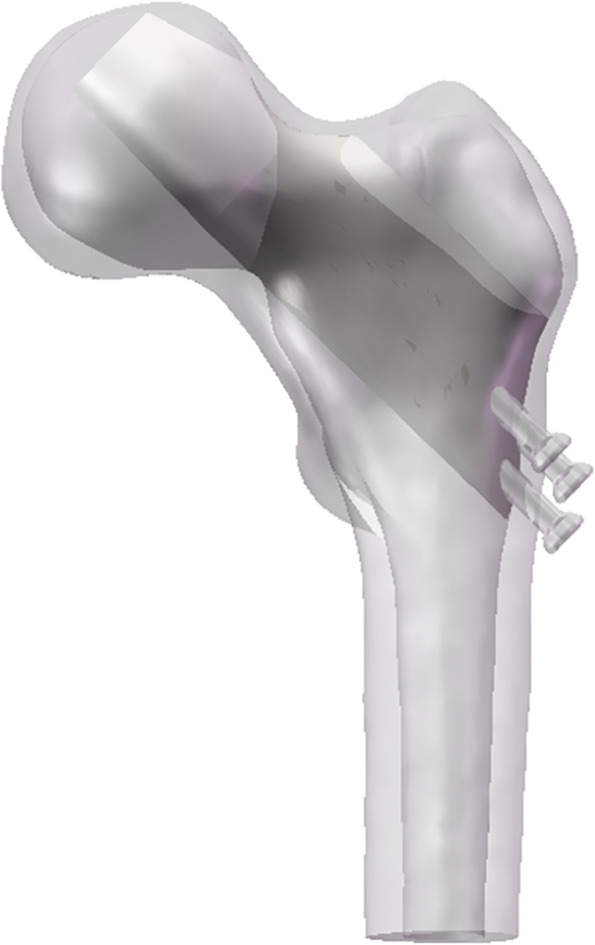

Fig. 1.

Radiographic data of a clinical femoral neck fracture case. A Coronal X-ray; B sagittal X-ray; C coronal CT; D sagittal CT. In the Figures, red arrows represent the high-density shadow around the cannulated screws

Following internal fixation of femoral neck fractures, and subsequentl fracture healing, the mechanical benefits of implants maintenance remain unclear. The rate of implant removal and the selection criteria for removal candidates are unknown, while the question of the implant’s post-healing effect on stress distribution remains controversial. Although both the femur and implants provide important mechanical effects, cases of postoperative femoral head collapse (Fig. 1) are still observed. Traditional cannulated screws are used as implant materials, and radiological examination of a collapsed necrotic femoral head sample 10 years after internal fixation showed numerous sclerotic and necrotic cavities formed around the implants (as shown in Fig. 1). We chose to use the term sclerotic cancellous bone (SCB) to describe this high-density distribution. Nevertheless, the longer the implants are retained, the more severe the osteosclerosis and osteonecrotic complications are likely to be, and the less likely it is that cancellous bone will develop normally.

Therefore, the formation mechanism of the sclerotic region is as follows: the lower screw of the normal inverted triangular internal fixation increases the stress concentration. The change in stress location following internal fixation then causes adaptive remodeling of cancellous bone, and the trabeculae around the internal fixation is transformed into plate-like trabeculae in order to take on greater stress. Microdamage around the implants initiates bone reconstruction and the easily displaced implants create unstable conditions for progressive thickening and expansion of the sclerosis. Finally, the formation of a high-density shadow is observed in the CT image, as seen in the presented case (Fig. 1).